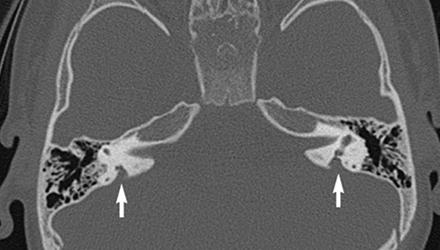

SLC26A4基因定位于人类染色体7q31,SLC26A4基因和大前庭导水管综合征相关突变位点的发现,证实SLC26A4是大前庭导水管综合征的责任基因。

我们平时提到的“一巴掌打聋”、“一跤摔聋”其实都与SLC26A4基因突变有关,绝大多数大前庭导水管综合征都是SLC26A4基因突变惹的祸。

SLC26A4基因突变导致的大前庭导水管综合征的典型表现为儿童时期的听力损失,90%的患者为双侧性,听力损失程度不一,可表现为接近正常或重-极重度。

病程可为稳定性、进行性或波动性,听力可逐步下降至全聋;跌倒、撞击等行为或无外界影响都可能引发听力的下降。